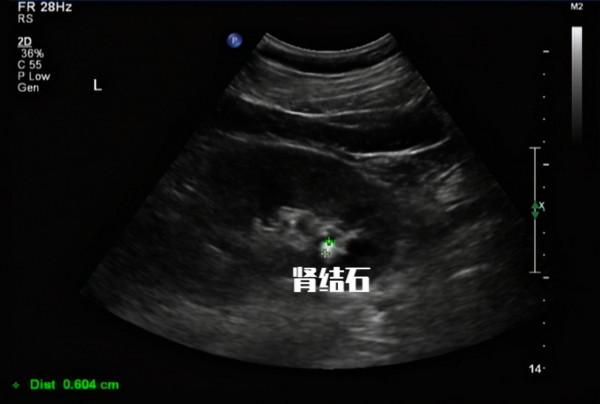

尿隱血陽性:常見於腎臟或尿道疾病、腎性高血壓、尿路結石、腎結核、惡性腫瘤、血紅蛋白尿症(不同血型輸血、溶血性貧血等)、肌紅蛋白尿症(骨骼肌破壞)。